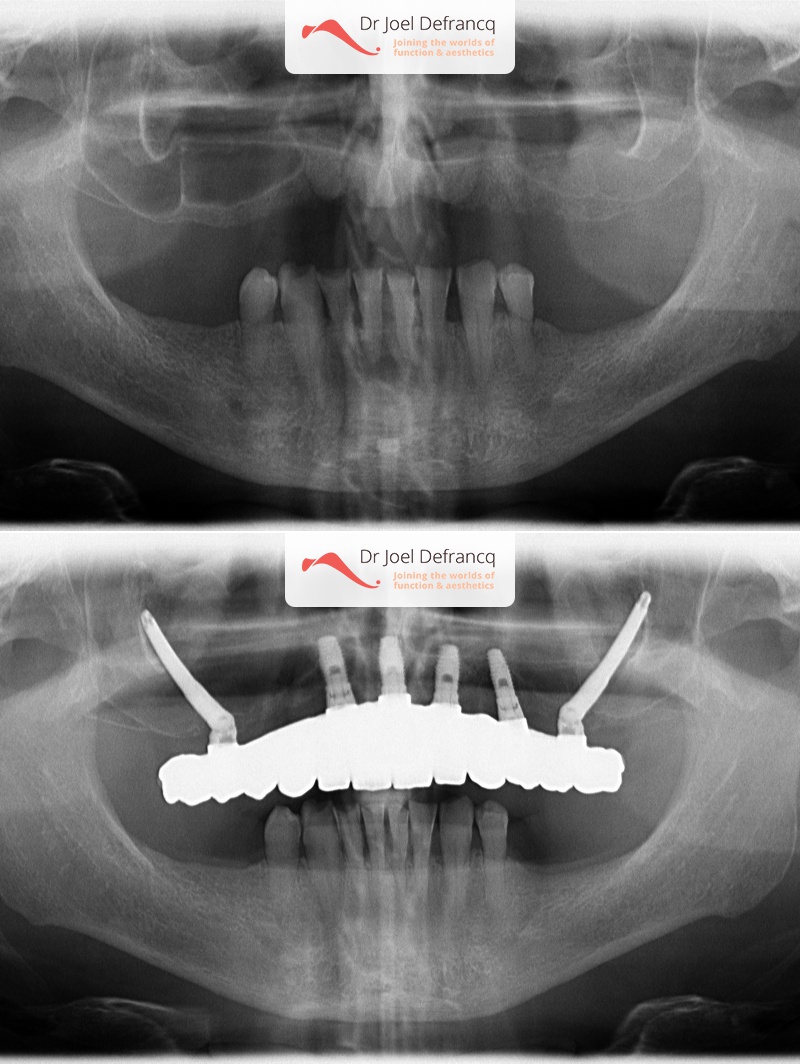

Behandeling tandheelkundige implantaten

- Vaste tanden op implantaten (bovenkaak)

- Zygoma implantaten